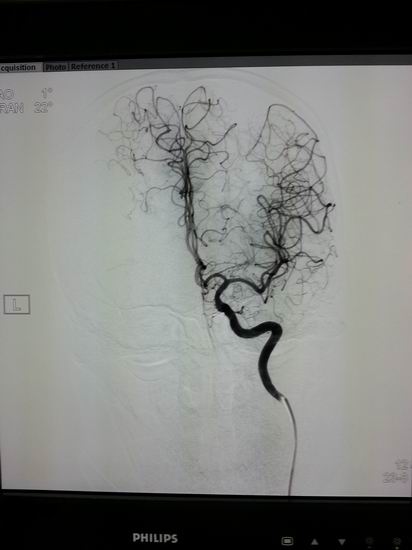

高档数字减影、血管造影系统 Allura Xper FD20

名称:高档数字减影、血管造影系统 Allura Xper FD20

主要功能:采用大平板科技,结合2K影像链,提供极佳图像细节解析能力,1250mA成像能力与“透心凉”高散热球管,“Refresh light”技术消除动态采集时的鬼影,图像质量更高。